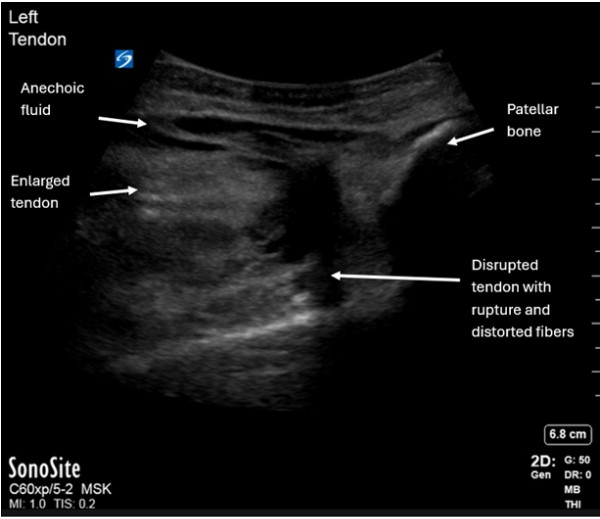

A healthy 34-year-old male presented with acute left knee pain and swelling after falling while playing basketball three days prior. The patient reported landing on his left knee and feeling a pop with immediate pain above the knee with subsequent swelling. He had a blood pressure of 155/85 mmHg, heart rate of 84 beats per minute, and was afebrile. On examination he had severe tenderness at his left distal thigh with a deformity superior to his patella. He had intact strength, sensation, and distal pulses in both legs but could not passively extend his left distal leg. Point-of-care ultrasound (POCUS) demonstrated a disrupted left distal quadriceps tendon with anechoic fluid, tendon enlargement near the insertion site, and tendon fiber distortion consistent with a complete tendon rupture. Left knee x-ray showed a joint effusion with soft tissue swelling anterior to the patella but no acute fracture.

Quadriceps tendon rupture can occur in emergency department (ED) patients with trauma or in patients with underlying pathology.[1,2,3] It is more common in patients over age 40 years old or with comorbidities including rheumatoid arthritis, systemic lupus erythematosus, gout, chronic kidney disease, secondary hyperparathyroidism, peripheral vascular disease, and diabetes mellitus.[4] Predisposing risk factors include degenerative tendon changes, tendon overuse injuries, previous injury, and partial tendon tears.[1,3] Complete quadriceps tendon rupture is diagnosed clinically by distal thigh tenderness, a suprapatellar hematoma, and inability to extend the distal leg against gravity.[1,2] MRI is the gold standard for diagnosis but is difficult to obtain in the ED or clinic.[3,4] Thus, tendon rupture diagnosis can be augmented by POCUS. POCUS findings include distortion of tendon fibers near the patellar insertion site, tendon enlargement, surrounding anechoic fluid, and tendon retraction (Figures 1 and 2).[3,4] Physicians should recognize clinical signs of tendon rupture and understand how to incorporate POCUS to expedite diagnosis and guide appropriate urgent surgical management.[4,5] Urgent orthopaedics surgical repair for complete ruptures is key to prevent permanent damage and disability, thus patients require close orthopaedics follow up.[4,5]

Figure 1: Longitudinal point-of-care ultrasound with complete rupture and retraction of left quadriceps tendon (white arrows) away from the patellar bone.

Figure 2: Point-of-care ultrasound longitudinal view of an enlarged hypoechoic quadriceps tendon with distortion of normal tendon fibers and surrounding anechoic fluid.